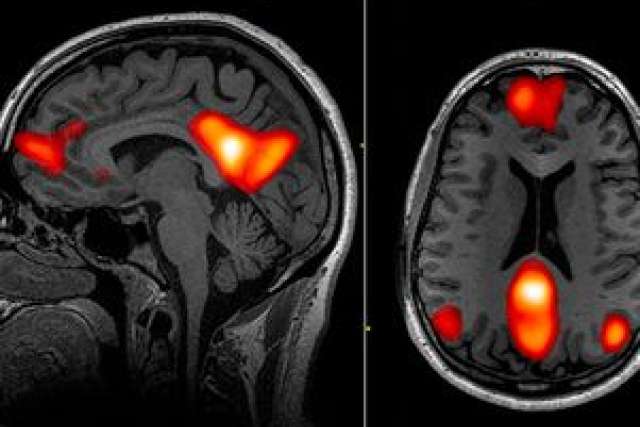

Using a functional MRI machine, or fMRI, the researchers scanned the brains of 42 people with OCD, ages 18 to 60, before and after four weeks of intensive, daily cognitive behavioral therapy. Researchers specifically analyzed how different areas of the brain activate in sync with each other — a property called functional connectivity — during a period of rest. Functional MRI does this by measuring blood flow in the brain, which correlates with neurons’ activity levels.

In addition, the scientists assessed the severity of participants’ OCD symptoms before and after the treatment, using a scaled system in which a lower score indicates less severe or less frequent symptoms. The researchers fed the participants’ fMRI data and symptom scores into a computer and then used machine learning to determine which people would respond. In machine learning, computers are trained to recognize common patterns in mountains of data by exposing them to numerous variations of the same thing.